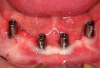

Four months later, overdenture attachments that permitted angle correction up to 60 degrees were attached to the implants by using a hex driver and were torqued per the manufacturer's recommendation (Figure 11).41 The attachments had a small screw-access hole that prevented food entrapment. Attachments are available in various heights.41 The height of each attachment should be predetermined by measuring the distance between the platform of the implant and the crest of the peri-implant tissue (Figure 12).47

Fig 11. Overdenture attachments attached to the implants (LOCATOR R-Tx, Zest Dental Solutions).

Figure 11